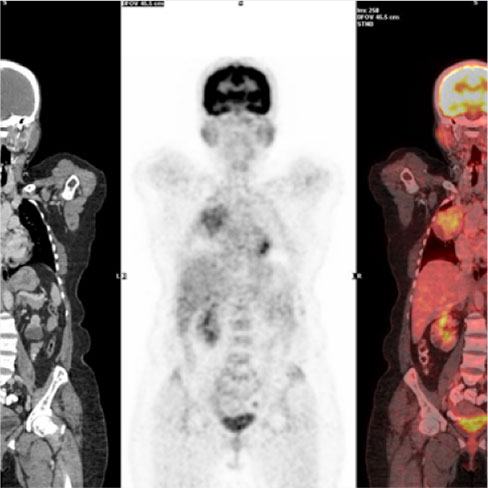

PSMA (Prostate-Specific Membrane Antigen) is a membrane glycoprotein that is an over-expressed manifold in prostate cancers and the expression increases with tumour aggressiveness, androgen independence, metastatic disease and disease recurrence.

PSMA PET Scan for prostate cancer is a prostate cancer-specific target diagnostic scan that provides both better sensitivity & high specificity at diagnosis for disease site localisation & improves detection at an earlier time point than with anatomical imaging techniques even at low PSA levels.